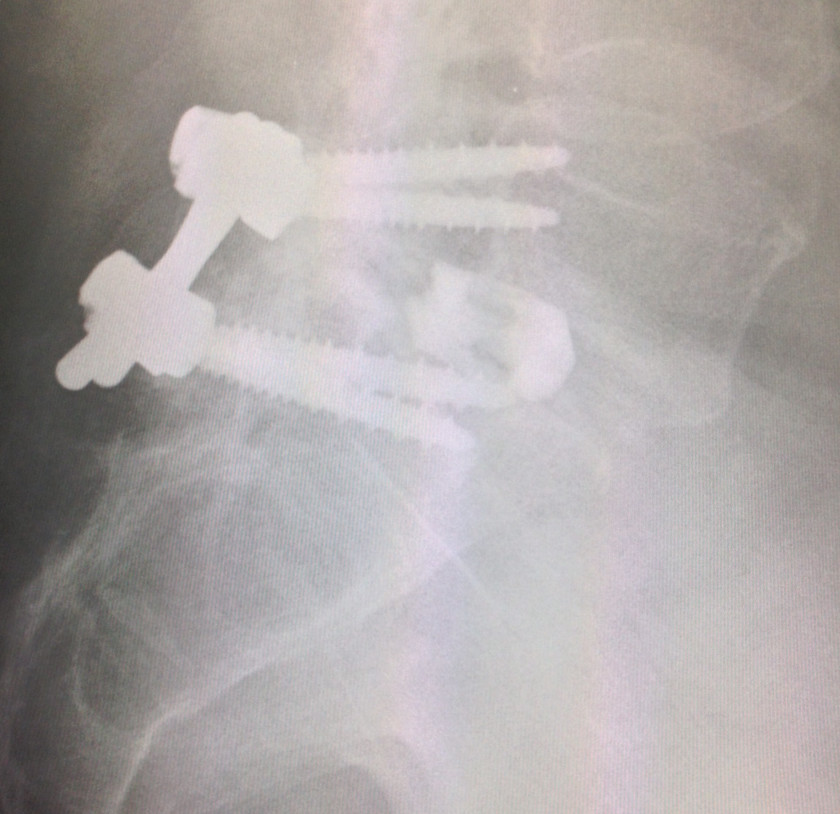

2016/11/04 脊椎外科専門医の迷作

前勤務先からだから・・・もう何年だろう❓

長い間、お付き合いさせて貰っている患者さん。

怪我をされて、2年ぶりに受診。ふと見れば、インスツルメンテーション術後。

スクリューの長さもスペーサーのポジションも素晴らしい😱

某私立大医学部の関連病院での『迷作』ですね。

もう、元整形外科医はノーコメント🙃。